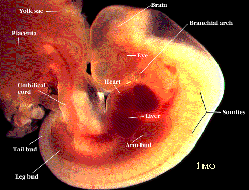

莫勒教授的著作裡在中世紀的標題下:『在中世紀,科學發展得很緩慢,人們對於胚胎學所知很少,而在穆斯林那裡,《古蘭經》卻提到人類的孕育與生長。人是由男女兩性的精液、卵細胞結合而受孕,並在多處指出人由受精卵而孕育,同時闡明了受精卵六天後像一粒種子般地植入母腹中。現今科學已證實了受精卵在著床後開始分化並在六天後開始生長。《古蘭經》也提到了受精卵逐漸生長,變成一團血塊。分裂後的受精卵,很像「阿來格」 (血塊)可以看到那個階段胚胎的外貌類似於「蛹」(如左圖所示)。圖中胚胎與「蛹」或水蛭在外形上沒有什麼二樣,在下一階段胚胎的外貌就像被咬過一口的奶酪或木片,如圖所示。胚胎已具有人的跡象。在過了四十一或四十二天後,胚胎已被認為完全是人的形象了,自此和動物的胚胎已不同了。在該階段胚胎已開始具有人的特徵,就像右圖中所示的樣子。